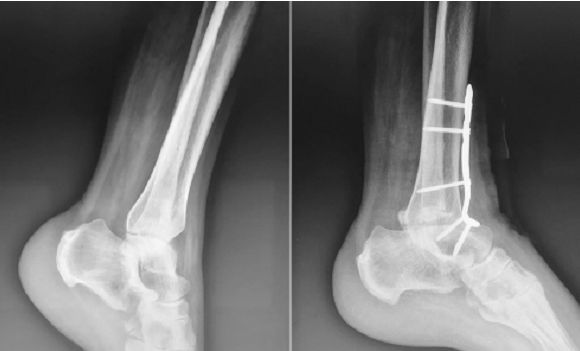

The picture above shows the X-ray films before and after surgery for traumatic ankle osteoarthritis with anterior locking plate internal fixation ankle joint fusion